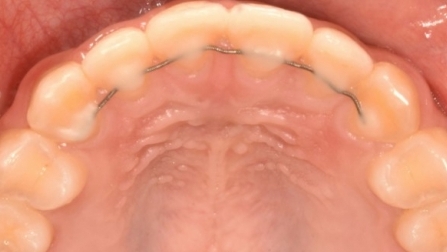

먼저 고정식 유지기가 있는데요. 치아 안쪽에 와이어를 부착해 치아를 고정하는 방법으로 가장 많이 사용되는 방법입니다. 단, 단점으로는 와이어 주변에 치석이 쌓일 가능성이 높아 치실 및 치아 관리는 필수라고 할 수 있습니다.